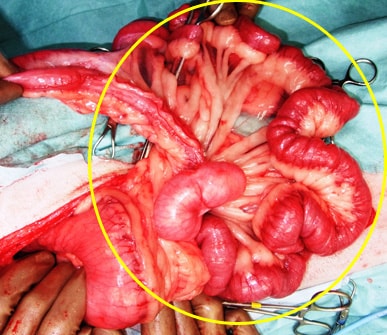

異物により胃から小腸全域に閉塞を起こし、整復した一例

ロープを飲み込んでしまって、胃から小腸全域で閉塞を起こし、小腸が蛇腹状にねじれて炎症を起こしています。 |

まずは胃内の大きなかたまりの異物を胃切開を行い、摘出し、胃を縫合します。 |

次に小腸全域につまったロープ状異物を小腸切開を行い全て摘出し、小腸吻合します。 |